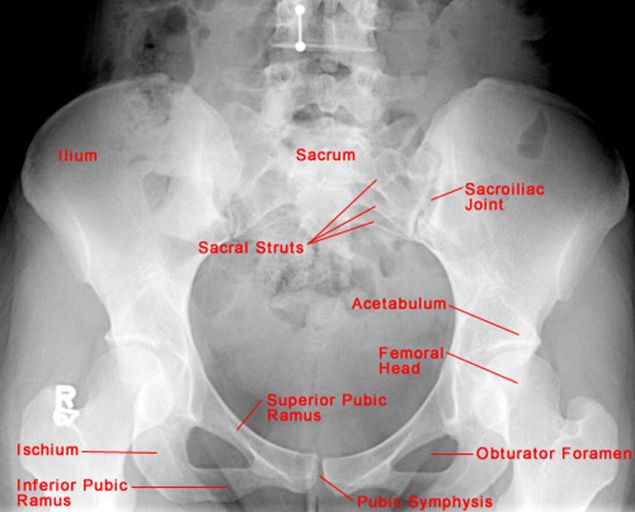

正常骨盆正位片

疼痛科怎么理疗疼痛科医生、康复理疗科医生、针刀针灸医生应掌握的常见骨科疾病X光片_https://www.jmylbn.com_新闻资讯_第47张